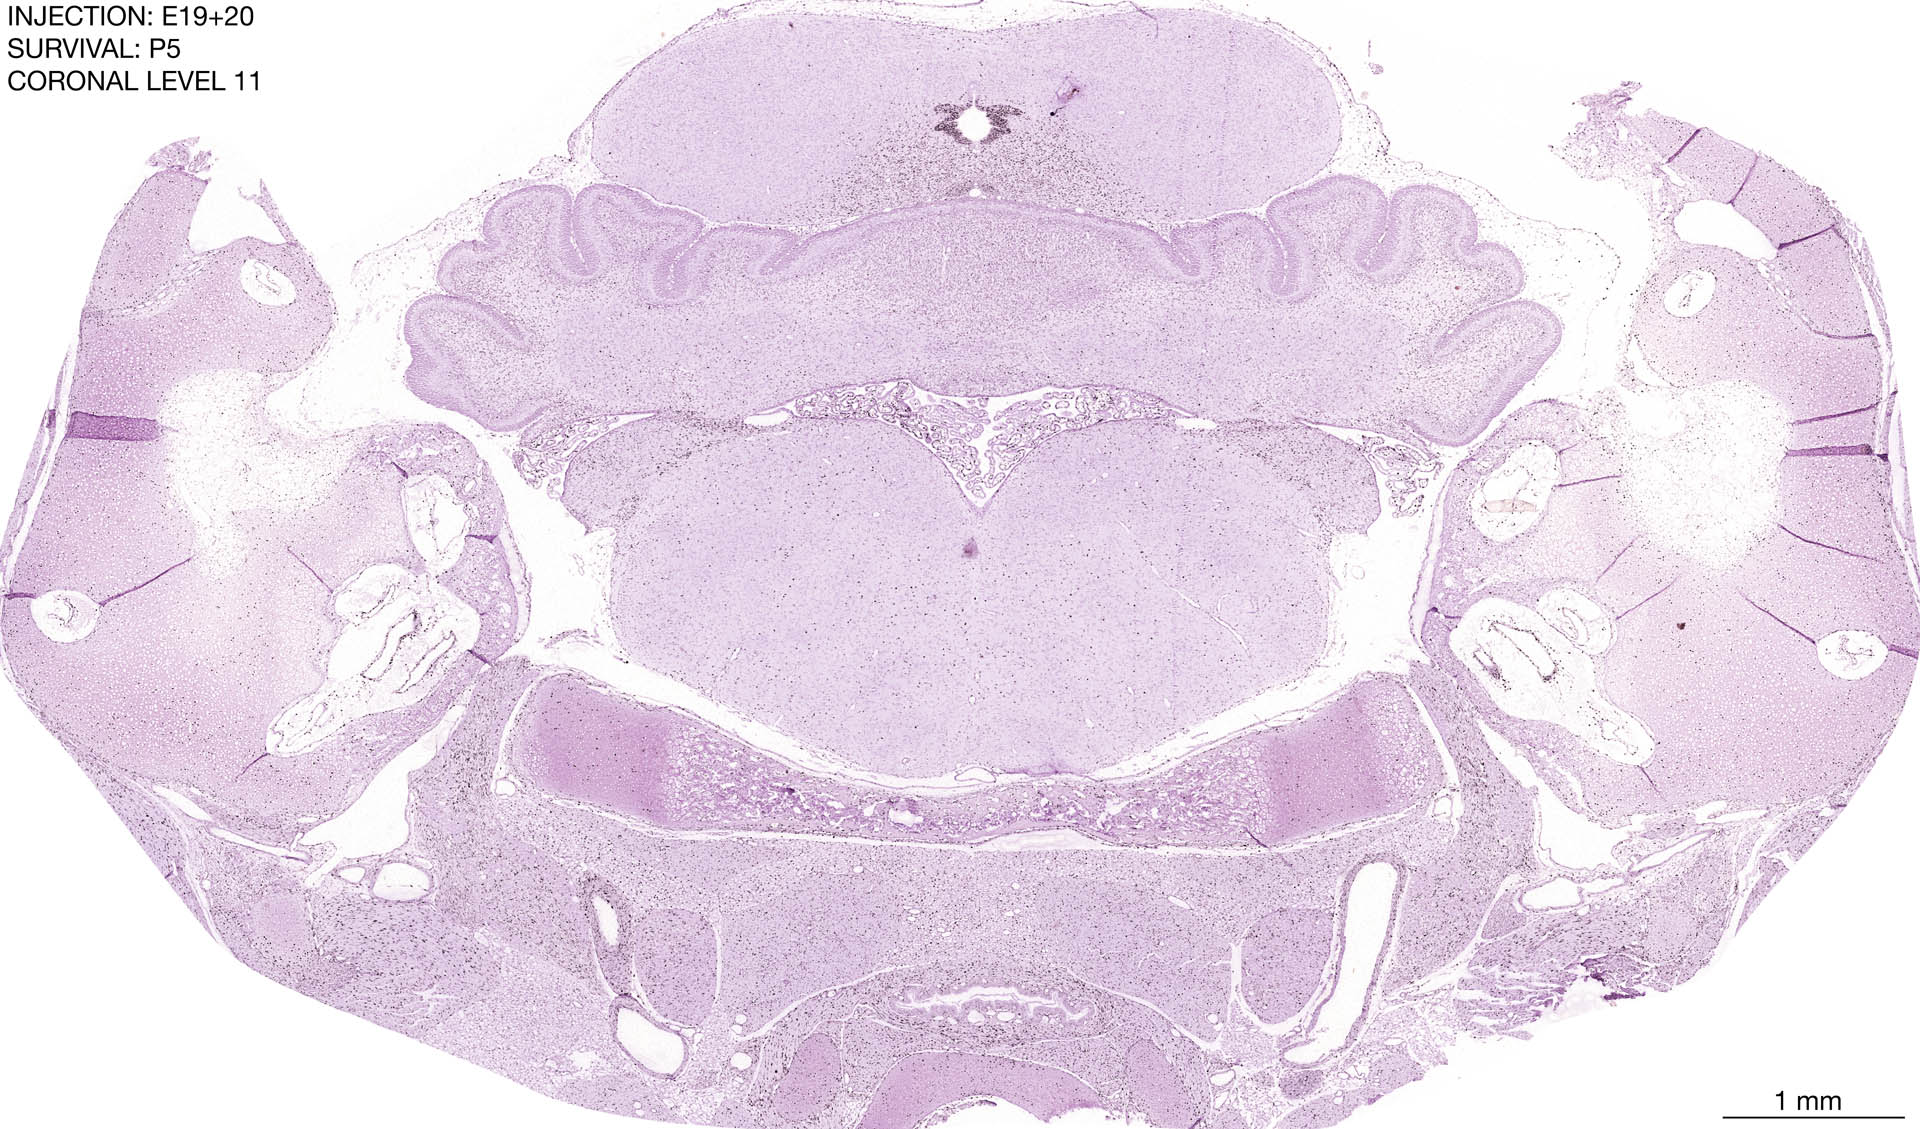

E19+20 P5 Survival The images below are from the brain of a rat that was exposed to tritiated thymidine on E19+20 and survived to P5. Download: Large | High Res Download: Large | High Res Download: Large | High Res Download: Large | High Res Download: Large | High Res Download: Large | High Res Download: Large | High Res Download: Large | High Res Download: Large | High Res Download: Large | High Res Download: Large | High Res Download: Large | High Res Download: Large | High Res Download: Large | High Res Download: Large | High Res Download: Large | High Res Download: Large | High Res Download: Large | High Res Download: Large | High Res Download: Large | High Res Download: Large | High Res Download: Large | High Res Download: Large | High Res Download: Large | High Res Download: Large | High Res Download: Large | High Res Download: Large | High Res Download: Large | High Res